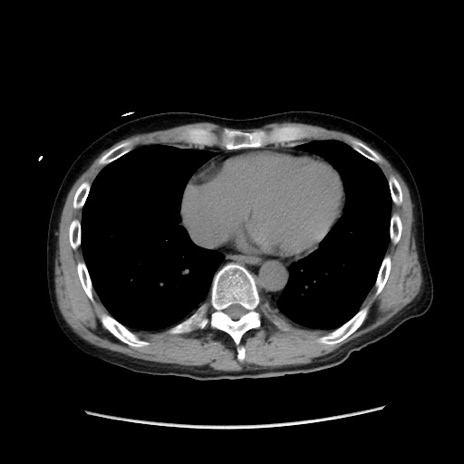

症例37(横断像)

【症例】40歳代 男性

【主訴】腹痛

【現病歴】4時間ほど前に電車に乗車中に臍部上より腹痛出現。徐々に増悪し起立困難となり、救急外来受診。生ものは数日食べていない。今朝お雑煮を食べた。

【身体所見】BT 36.8℃、BP 117/84mmHg、HR 91/min、SpO2 97%、苦悶様、腹部:臍上部広範囲圧痛あり、反跳痛±

【データ】WBC 8100、CRP 0.03